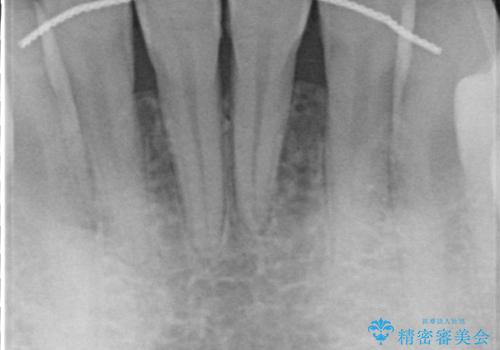

- 他院で矯正治療を終えた結果、下顎前歯の歯肉が退縮してしまい、歯根が見えていることが気になるとのことで来院された患者様です。

歯肉退縮に対して、上顎からの結合組織移植術(CTG)により、歯根の被覆を行うとともに、歯肉の厚みを増すことで将来の退縮リスクを抑制することとしました。